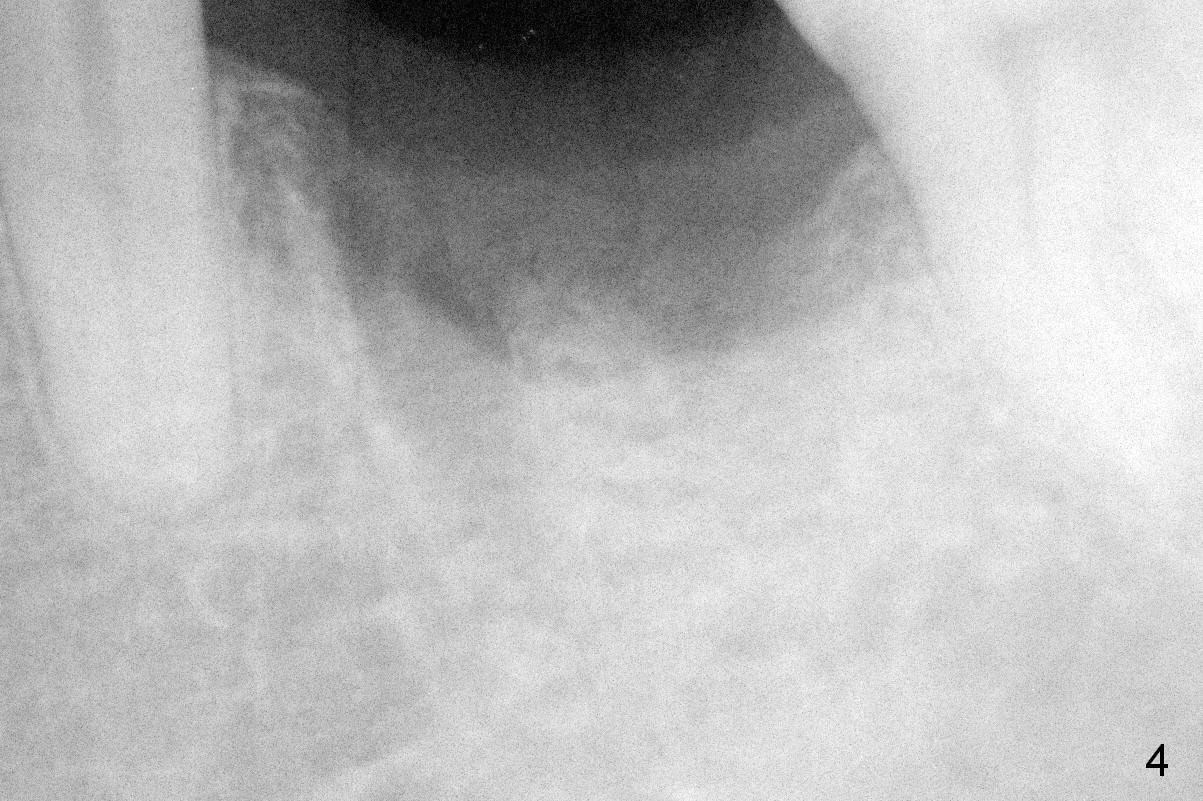

The mesial and distal crests of the tooth #19 were even for a 50-year-old man 7 years ago. Three years later, swelling developed around the distal root with bone loss (Fig.2 *). Three months later, localized swelling occurred (Fig.3 *) with oozing. The patient had thrombopenia (platelet 40 K). The tooth was extracted with suture. There is distolingual root tip resorption. Two months and a half later (Fig.4), a 6x17 mm implant was placed (Fig.5). The implant osteointegrated 5 months postop (Fig.6). The distal crest re-appears 5 months (Fig.7), 2 years (Fig.8) and 2 years 8 months (Fig.10) post cementation. At the last appointment, the patient complained of pain and swelling at #30 with mesial bone loss (Fig.10 *), as compared to Fig.9 taken 9 years ago. The mesiolingual pocket is deep. After scaling and Chlorhexidine irrigation, Arestin is locally administered.